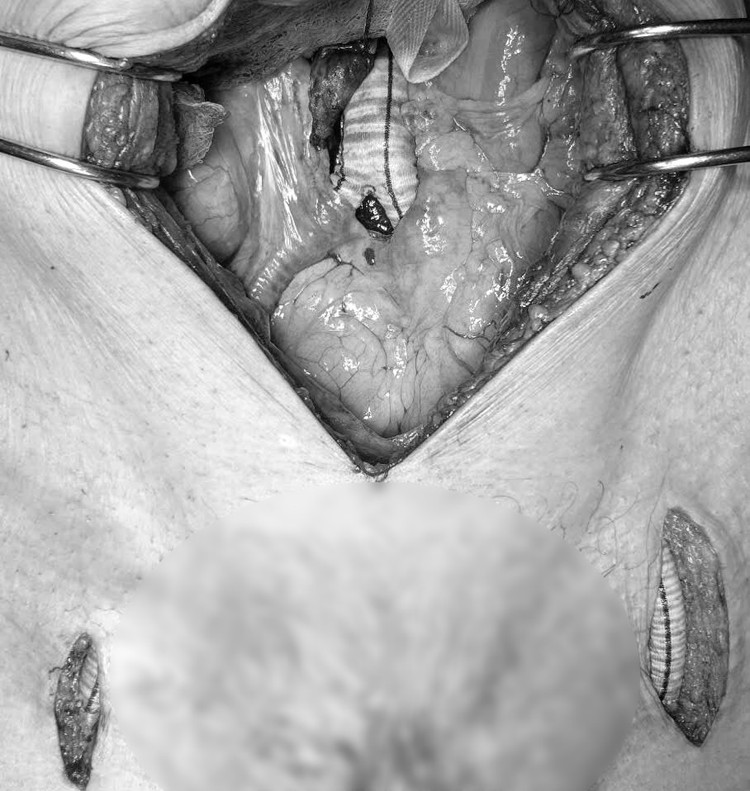

machchi1.jpg

Phẫu thuật bắc cầu mạch chi cho bệnh nhân 84 tuổi - Ảnh BVCC